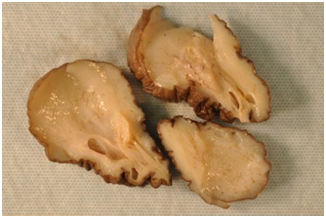

The soft tissue sonogram showed a mass measuring approximately 5.3 cm x 4.7 cm x 2.3 cm, which was projecting from a vascular stalk on the labial majora. The lesion was mildly heterogeneous in echotexture, appearing predominantly solid (Figure 3). The patient underwent wide local excision of the mass. Pathology of the mass showed an aggressive angiomyxoma. The pathologist also noted “this mesenchymal lesion is locally aggressive with a high risk for recurrence if incompletely excised. Although the pedicle margin of resection appears free of the lesional process further clinical concern may warrant conservative excision at the site of lesion attachment”. It was also noted that the mass was hypocellular and composed of stellate cells with an ill-defined cytoplasm distributed through a finely fibrillar and myxoid matrix. The nuclei were bland and mitoses were not present. There were numerous thin and thick walled blood vessels that blended with the surrounding matrix (Figures 5-8).

Figure 4 The cut surface of the tumor is gray-white and shiny due to the glycosaminoglycan (GAG) of the matrix.